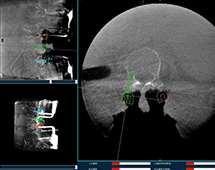

机器人辅助腰椎后路侧弯矫形手术方案解析

机器人辅助腰椎后路侧弯矫形手术是什么原理?下面带来一例机器人辅助腰椎后路侧弯矫形手术方案,该手术在南京医科大学第二附属医院进行,所用设备为普爱脊柱外科手术机器人PL300B+三维C形臂PLX7500A。...